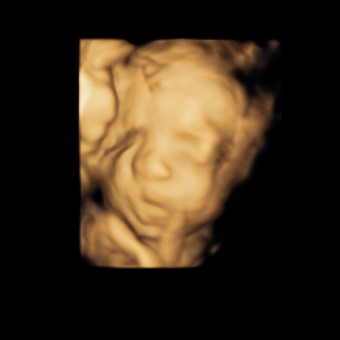

Damaris Amaya

Winchester, VA